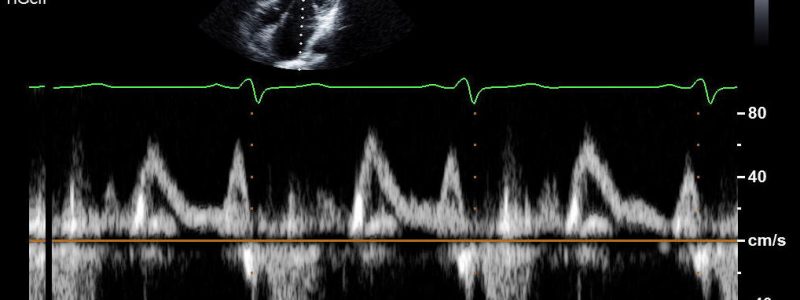

- Ich biete alle in der Praxis möglichen kardiologischen Untersuchungen und Möglichkeiten der Nachkontrolle inklusive implantierte elektronischer Geräte mit moderner Technologie an und arbeite mit allen kardiologischen Kliniken der Schweiz und dem Röngteninstitut IMAMED für weitergehende Untersuchungen zusammen. Ich investiere auch in technologische Fortschritte, die eine bessere oder weniger belastende Diagnostik erlauben. Aktuell habe ich das neueste Echokardiografiegerät von Philips als einer der Ersten in der Schweiz erworben (EPIC CVx). Ausserdem ist die Auswertung von Langzeit-EKG’s auf den neuesten Stand gebracht worden.